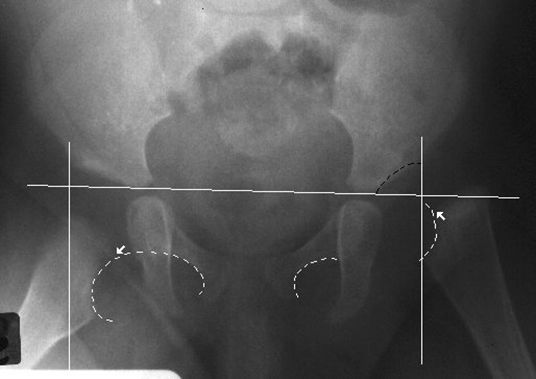

正常骨盆正位片

疼痛科怎么理疗疼痛科医生、康复理疗科医生、针刀针灸医生应掌握的常见骨科疾病X光片_https://www.jmylbn.com_新闻资讯_第47张

髋关节后脱位

疼痛科怎么理疗疼痛科医生、康复理疗科医生、针刀针灸医生应掌握的常见骨科疾病X光片_https://www.jmylbn.com_新闻资讯_第48张

髋关节前脱位

疼痛科怎么理疗疼痛科医生、康复理疗科医生、针刀针灸医生应掌握的常见骨科疾病X光片_https://www.jmylbn.com_新闻资讯_第49张

先天性髋脱位

疼痛科怎么理疗疼痛科医生、康复理疗科医生、针刀针灸医生应掌握的常见骨科疾病X光片_https://www.jmylbn.com_新闻资讯_第52张

常见髋关节测定线

疼痛科怎么理疗疼痛科医生、康复理疗科医生、针刀针灸医生应掌握的常见骨科疾病X光片_https://www.jmylbn.com_新闻资讯_第53张